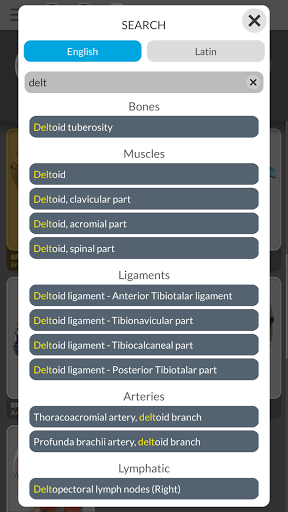

"Anatomía - Atlas 3D" permite estudiar la anatomía humana de forma fácil e interactiva.

nervioso • Sistema respiratorio • Sistema digestivo • Sistema urogenital (masculino y femenino) • Sistema endocrino • Sistema linfático • Sistema ocular y auditivo CARACTERÍSTICAS • Interfaz sencilla e intuitiva • Rotar y hacer zoom en cada modelo en el espacio 3D • Opción para ocultar o aislar uno o varios modelos seleccionados • Filtro para ocultar o mostrar cada sistema • Función de búsqueda para encontrar fácilmente cada parte anatómica • Función de marcador para guardar vistas personalizadas • Rotación inteligente que mueve el centro de rotación automáticamente • Función de transparencia • Visualización de músculos a través de niveles de capas desde las superficiales hasta las más profundas • Al seleccionar un modelo o un pin, aparece el término anatómico relacionado • Descripción de los músculos: origen, inserción, inervación y acción • Mostrar/ocultar interfaz de usuario (muy útil con pantallas pequeñas) MULTILINGÜE • Los términos anatómicos y la interfaz de usuario están disponibles en 11 idiomas: latín, inglés, francés, alemán, italiano, portugués, turco, ruso, español, Chino, japonés y coreano • Los términos anatómicos se pueden mostrar en dos idiomas simultáneamente REQUISITOS DEL SISTEMA • Android 8.0 o posterior, dispositivos con al menos 3 GB de RAM Reversi